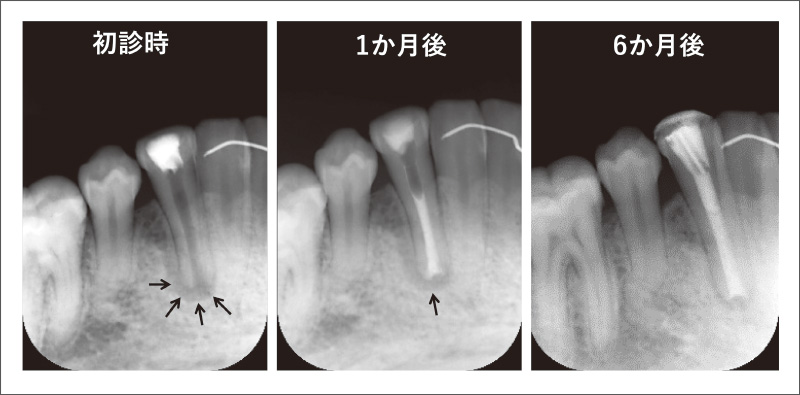

![[写真] 「メタシールSoftペースト」が根尖孔から溢出した症例](/academic/dentalmagazine/wp-content/uploads/sites/2/2025/09/194-1_photo04.jpg)

図4 「メタシールSoftペースト」が根尖孔から溢出した症例

シーラーが溢出(黄矢印)したが症状は出現せず、根管充填1年後には溢出シーラーは骨に囲まれていた。

「メタシールSoftペースト」は流動性が高いため、特に根尖孔が大きい場合には、単独で根管充填後に仮封材を根尖方向に押すと、シーラーが根尖孔から溢出することがあるので注意したほうが良い(図4)。